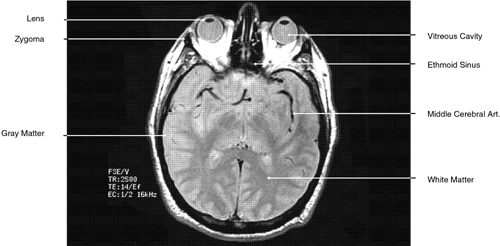

Fig. 32. A. Axial computed tomography soft tissue image at the level of suprasellar cistern. B. Axial computed tomography soft tissue image at the level of thalamus. C. Axial T1-weighted image at the level of thalamus.